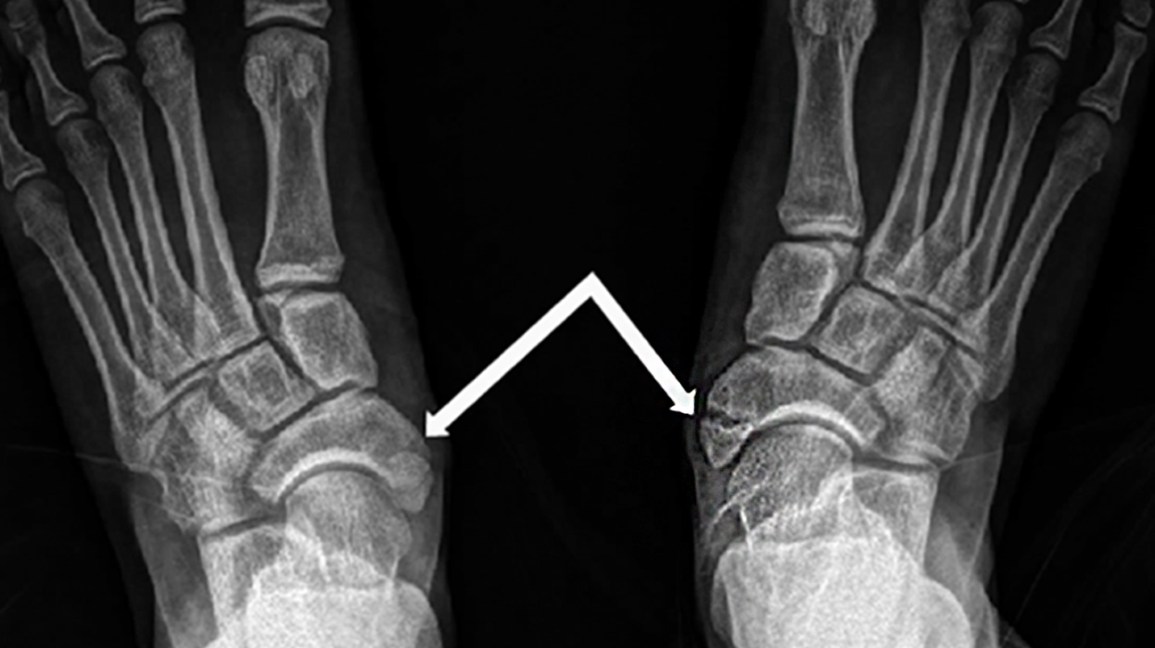

- Foot